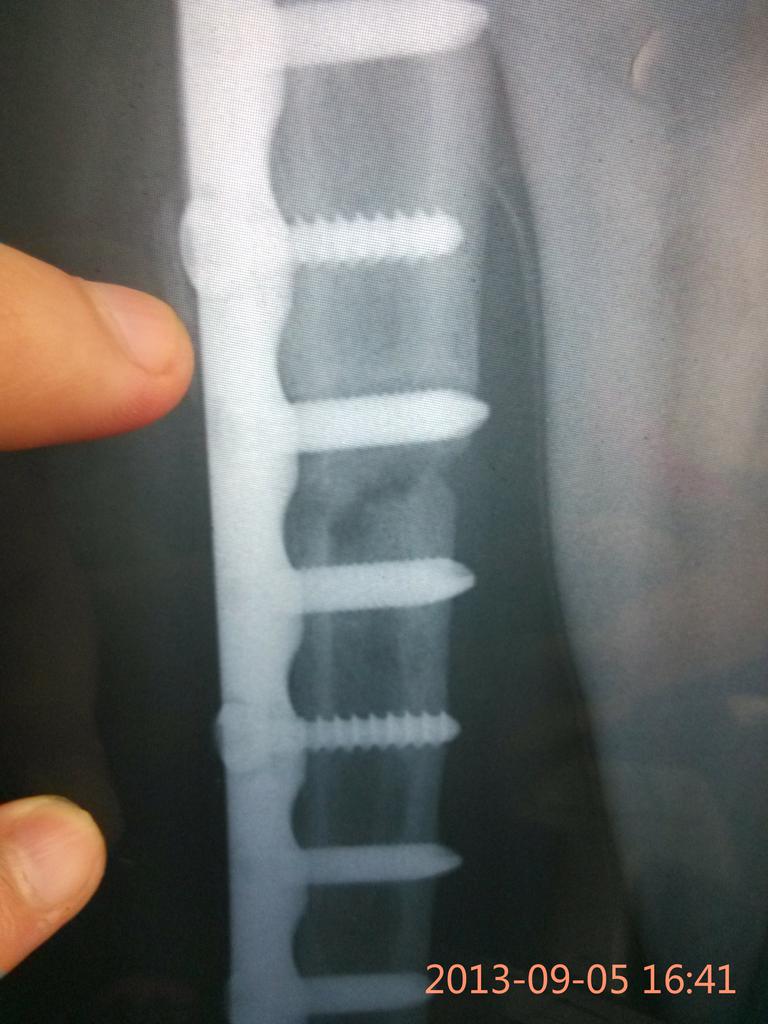

上面是术后一年的

有个钉子怎么离断端那么近?